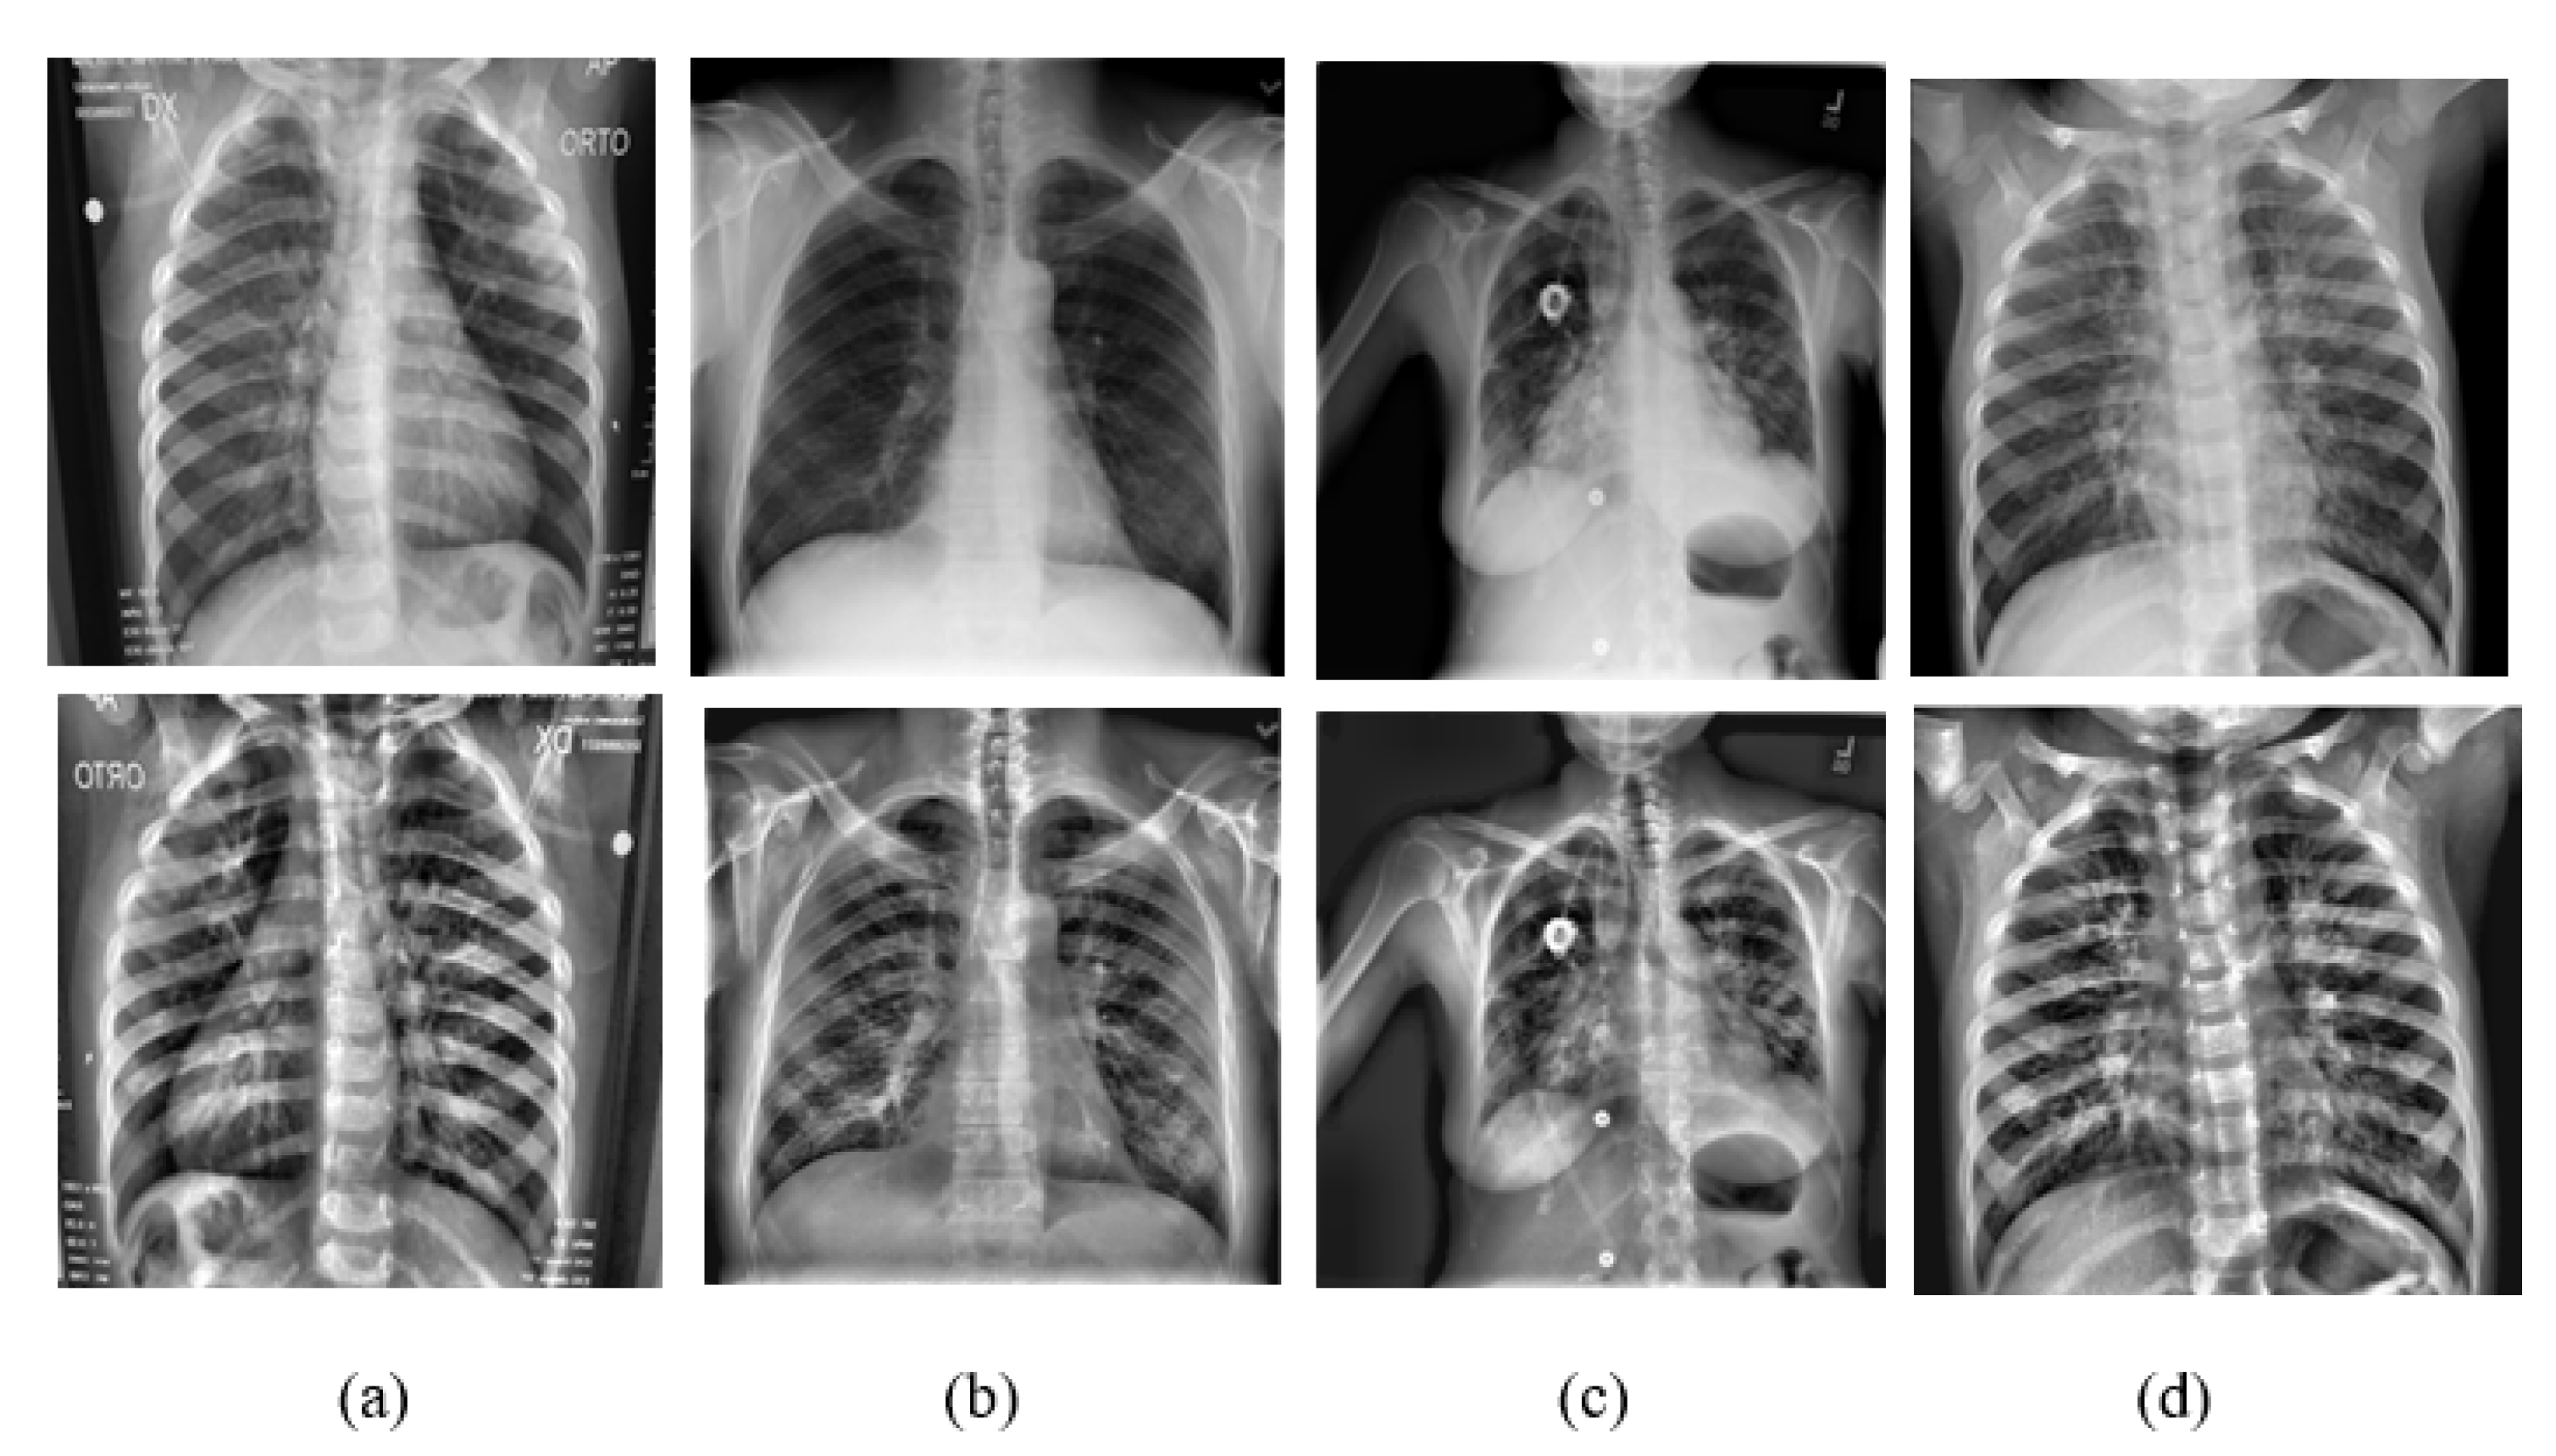

A team of researchers in collaboration with medical doctors compiled a dataset containing images of lung X-rays for COVID-19-positive cases along with normal and viral pneumonia images [22,44]. The dataset was categorized into four classes: (i) 3615 X-ray images of COVID-19 data, which were collected from different publicly accessible datasets, online sources, and published papers; (ii) 10,192 X-ray images of normal data; (iii) 1345 viral pneumonia data; and (iv) 6012 lung opacity X-ray images collected from the Radiological Society of North America. The final dataset employed in this research has 21,164 images. All the images are in Portable Network Graphics (PNG) file format and resolution is 299 299 pixels. Sample shots of the four classes are shown in Figure 7.

Figure 7. Shown here are some sampling images of the classes (a) COVID-19 case, (b) normal case, (c) viral pneumonia, and (d) lung opacity. The original images are in the first row and the corresponding CLAHE images are in the second row.